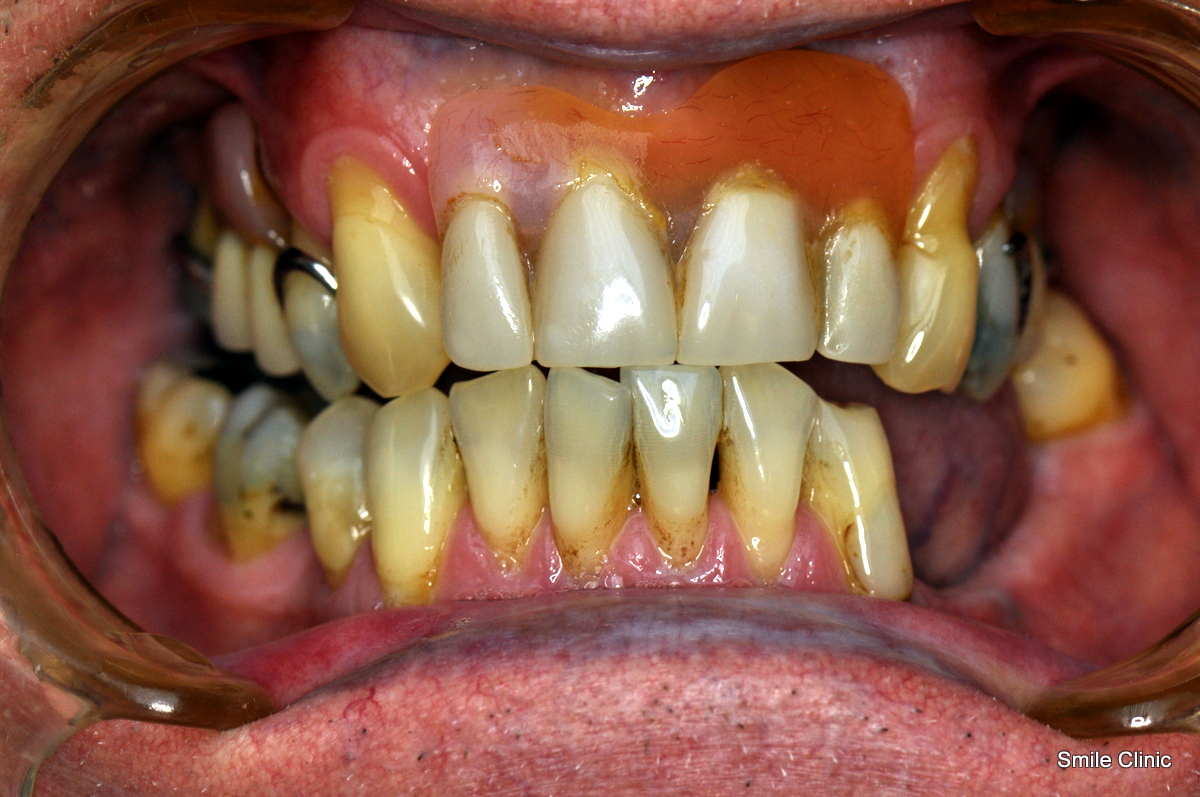

He had been wearing false upper teeth for some time, and decided to finally get rid of it by opting for the “all on 6” dental implant procedure giving him 12 new, fixed teeth for his upper jaw on 6 dental implants, as well as a crown tooth bridge of 4 teeth for the bottom jaw towards the back for added eating strength.

As you can see from the photographs, David opted for a natural look, complementing his original teeth – with an improved smile & confidence.